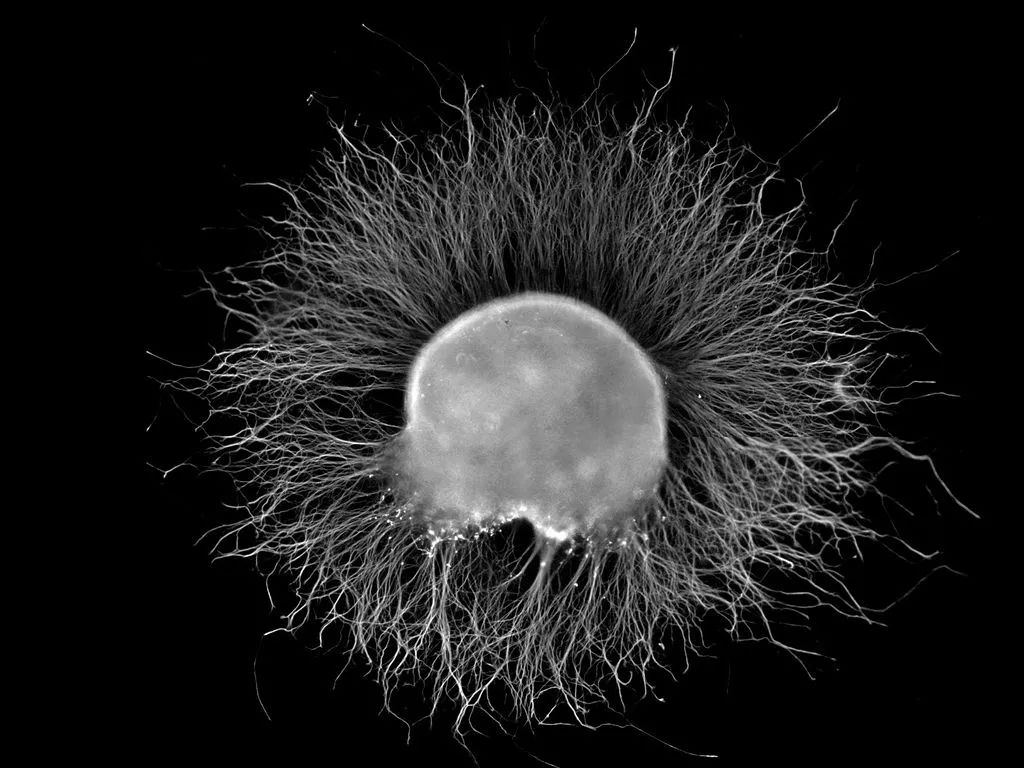

电子显微镜的水痘带状疱疹病毒约放大倍数为150,000倍

原来在治疗水痘的过程中,人体免疫系统确实把体内大多数的VZV病毒消灭掉。但仍会残留一些不能被血清中的抗体完全中和的VZV病毒。这些病毒发挥着自己天然亲近神经的特性,顺着皮肤的上皮感觉神经末梢不断逃离免疫大军攻击。最后,它们躲进了脊髓后根神经节的神经元或是颅神经的感觉神经节里,并在长期定居了下来。

要知道,这两大类神经节恰好是主管感觉的神经的汇聚地。从这里发出的感觉神经遍布于全身皮肤,会让人感觉到痛、冷、热等。可想而知,有朝一日当它们重新爆发时会有多痛苦。